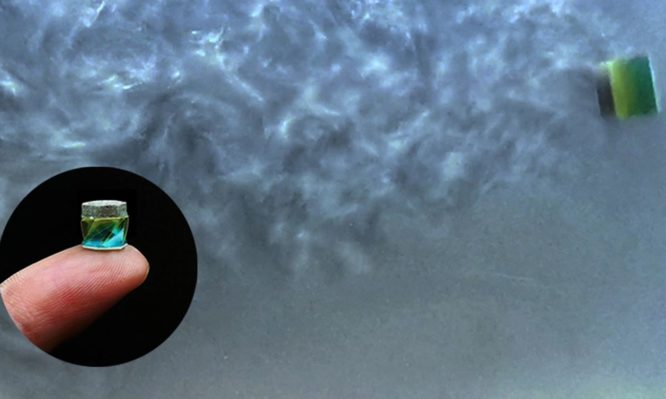

Το ρομπότ στο μέγεθος μπιζελιού ελέγχεται από μαγνήτες και μεταφέρει ωφέλιμα φορτία φαρμάκων απευθείας σε όγκους, θρόμβους αίματος, ή μολύνσεις. Το “origami millirobot”, όπως το λένε οι ερευνητές, πρόκειται να φέρει επανάσταση στην ιατρική, αντικαθιστώντας χάπια, ή ενδοφλέβιες ενέσεις, που μπορεί να προκαλέσουν απειλητικές για τη ζωή παρενέργειες.

Το ρομπότ έχει πλάτος λιγότερο από το 0,8 cm. Είναι εξοπλισμένο με μαγνητικές πλάκες και μπορεί να αλλάξει κατεύθυνση με ευκολία.